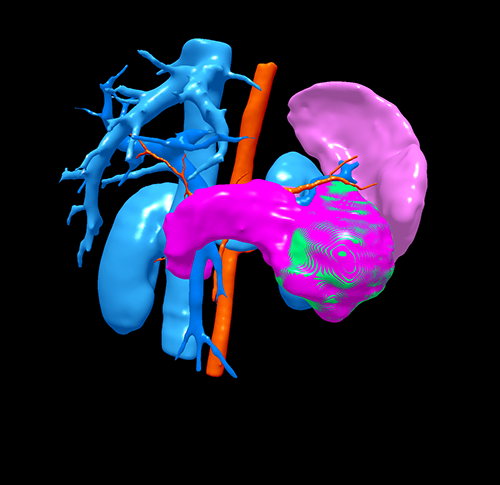

胰体尾实性假乳头状瘤---腹腔镜胰体脾切除